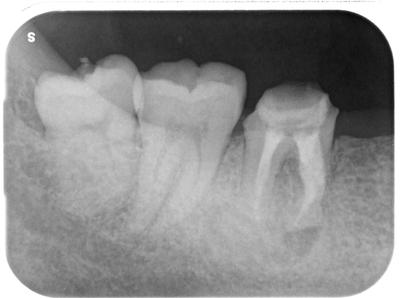

6┐腫脹、痛みにて来院。

近心根に破折ファイル片が残存。

CBCTも撮影し、最初は簡単に除去できると思っていたが、深くに太いファイルが食い込み苦戦した。